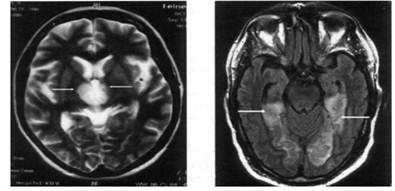

МРТ головного мозга на 4-й день от начала инсульта:

а - гиперинтенсивные участки на T1-взвешенном изображении (показано стрелкой); б - гипоинтенсивные участки на Т2-взвешенном изображении (показано стрелкой) соответствуют геморрагическому инфаркту в затылочно-теменном участке левого полушария головного мозга

| MPT головного мозга на 3-й день от начала инсульта (Т2-взвешенное изображение, аксиальная плоскость): двусторонний таламический инфаркт; на уровне подкорковых структур визуализируются симметричные (больше справа) гиперинтенсивные большие светлые участки в таламусе (показано стрелками), которые отвечают ишемическому инфаркту | МРТ головного мозга больного через 24 ч от начала заболевания (Т2ТИРМ-взвешенное изображение): симметрично с обеих сторон визуализируются большие гиперинтенсивные очаги инфаркта в медио-височно-затылочных областях головного мозга (показано стрелками) |